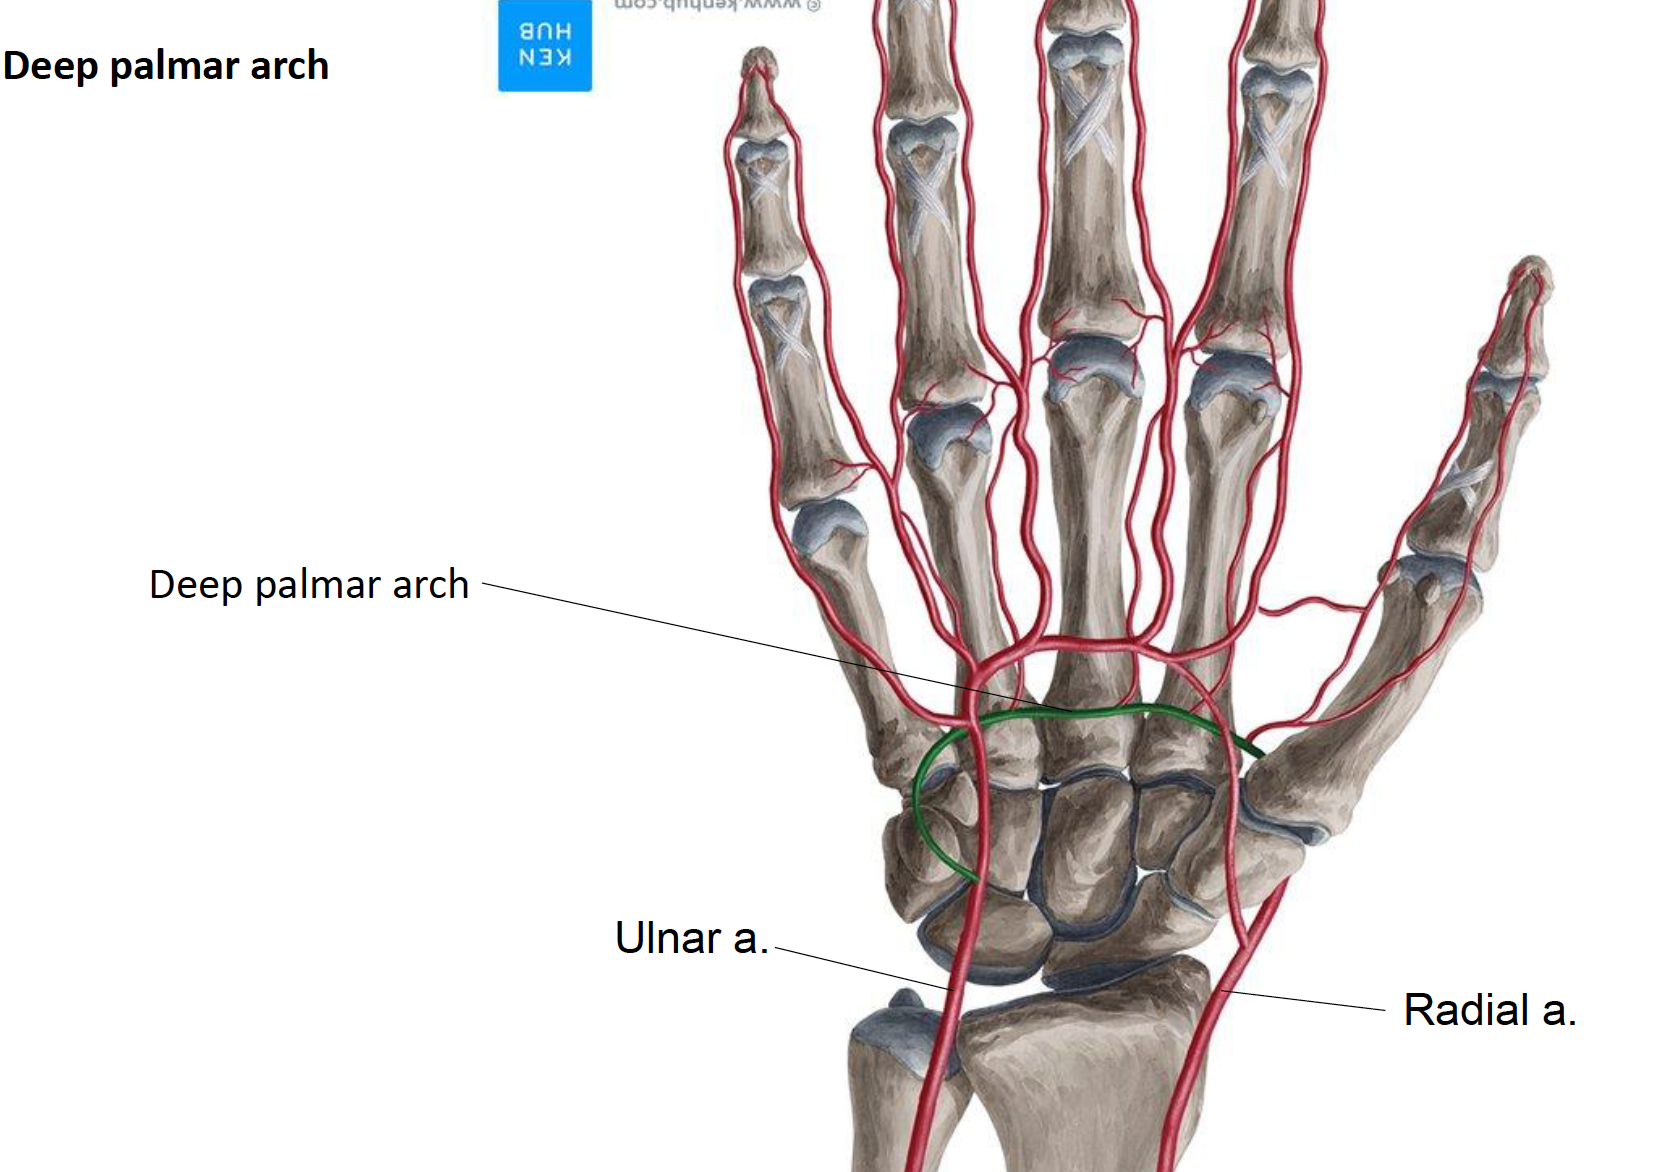

Carpi

由外而內:

Palm

Superficial

Deep